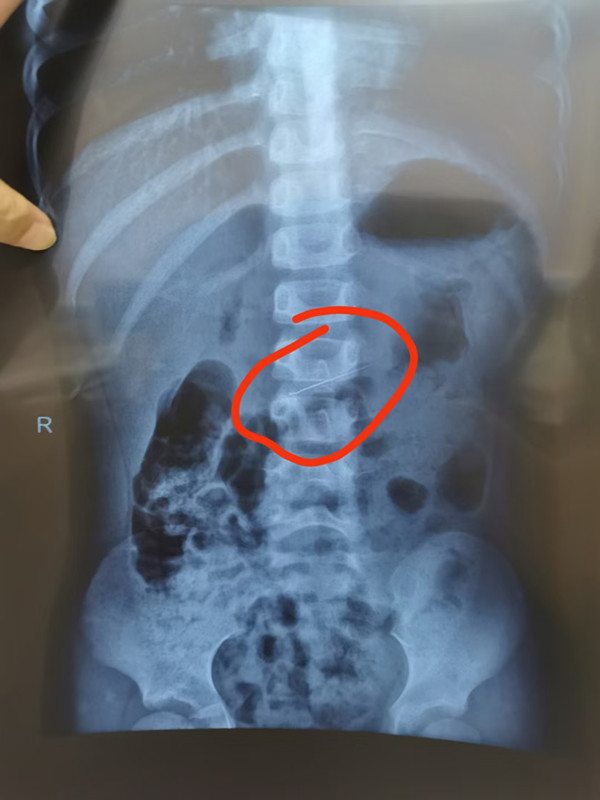

针在胃,立即手术图片

耳鼻喉科医生马上联系内镜中心,副主任边鹏火速赶来。经检查,针真的在悠悠胃里。情况紧急,为避免针划伤胃壁、损伤肠道,需要立即手术取针。内镜中心医生立刻给悠悠做了术前采血,一系列准备完毕后,悠悠全麻进入手术室。

3分钟,取出4厘米修牙针图片

在手术团队成员的密切配合下,仅用3分钟,修牙针被成功取出,悠悠的消化道毫无损伤。经测量,悠悠吞的修牙针足有4厘米长。好在,悠悠就诊及时,医护人员手术及时,让悠悠转危为安。从悠悠入院到异物取出,仅40分钟。